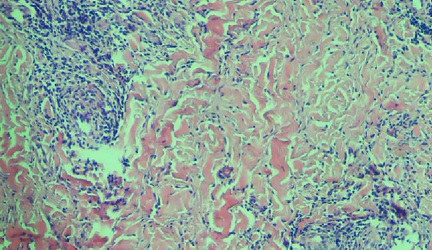

Leishmaniasis background and histology presentation. The World Health Organization (WHO) has selected cutaneous leishmaniasis as a neglected tropical disease (NTD) with growing, uncontrolled, and ignored infection affecting millions of people every year [14, 9]. It is unfortunately one of the world’s most neglected poverty-related diseases, affecting the poorest people in developing countries and it is associated with risk factors like malnutrition, immune system deficiency, migration, inadequate education, illiteracy, gender inequality, and a shortage of services [1]. Furthermore, only eight countries in the world contribute to 90% of leishmaniasis cases: Afghanistan, Algeria, Brazil, Iran, Pakistan, Peru, Saudi Arabia, and Syria [12]. It is a vector-borne infection caused by the protozoan parasite Leishmania. The vector is the female sand-fly. The lesions of cutaneous leishmaniasis vary in presentation ranging from a single self-limited skin lesion to multiple large destructive and ulcerated lesions on mostly the exposed parts of the body such as face, forearms, and lower legs [2]. Skin biopsy is considered the gold standard method for confirmation of diagnosis. The presence of large epitheloid granulomas and small hematoxylinophilic LD bodies (that are round, uniform in appearance, intracytoplasmic and sometimes distributed around the outer rim of the vacuoles) is critical for diagnosis and confirmation of leishmaniasis [4]. Large granulomas are visible at 10X but the smaller hematoxylinophilic bodies (around 3-4mm in size) are usually visible at 40X and can easily be missed if they are few in number, leading to misdiagnosis. Specialized dermatopathologists are the only ones who can diagnose these accurately based on patient history, clinical features, and laboratory diagnosis. It is thus critical to share the digitized slides of these cases from rural poor remote areas with dermatopathologists (mostly residing in urban centers) for quick diagnosis and accurate management of the patient.

We demonstrate our WSI creation workflow on Leishmaniasis cases, as shown in Figures 1 and 4. An expert pathologist reviewed the cases and annotated granulomas as well as LD bodies on the stitched images and our generated images in Figure 4. To show generalizability of our approach, we also show results on core biopsies of breast, duodenum, stomach, liver, and lymph nodes (Figure 5).